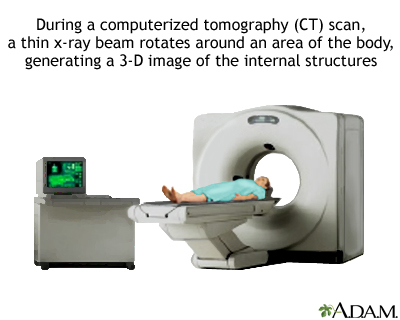

A chest CT (computed tomography) scan is an imaging method that uses x-rays to create cross-sectional pictures of the chest and upper abdomen.

- You'll lie on a narrow table that slides into the center of the scanner. Once you are inside the scanner, the machine's x-ray beam rotates around you.